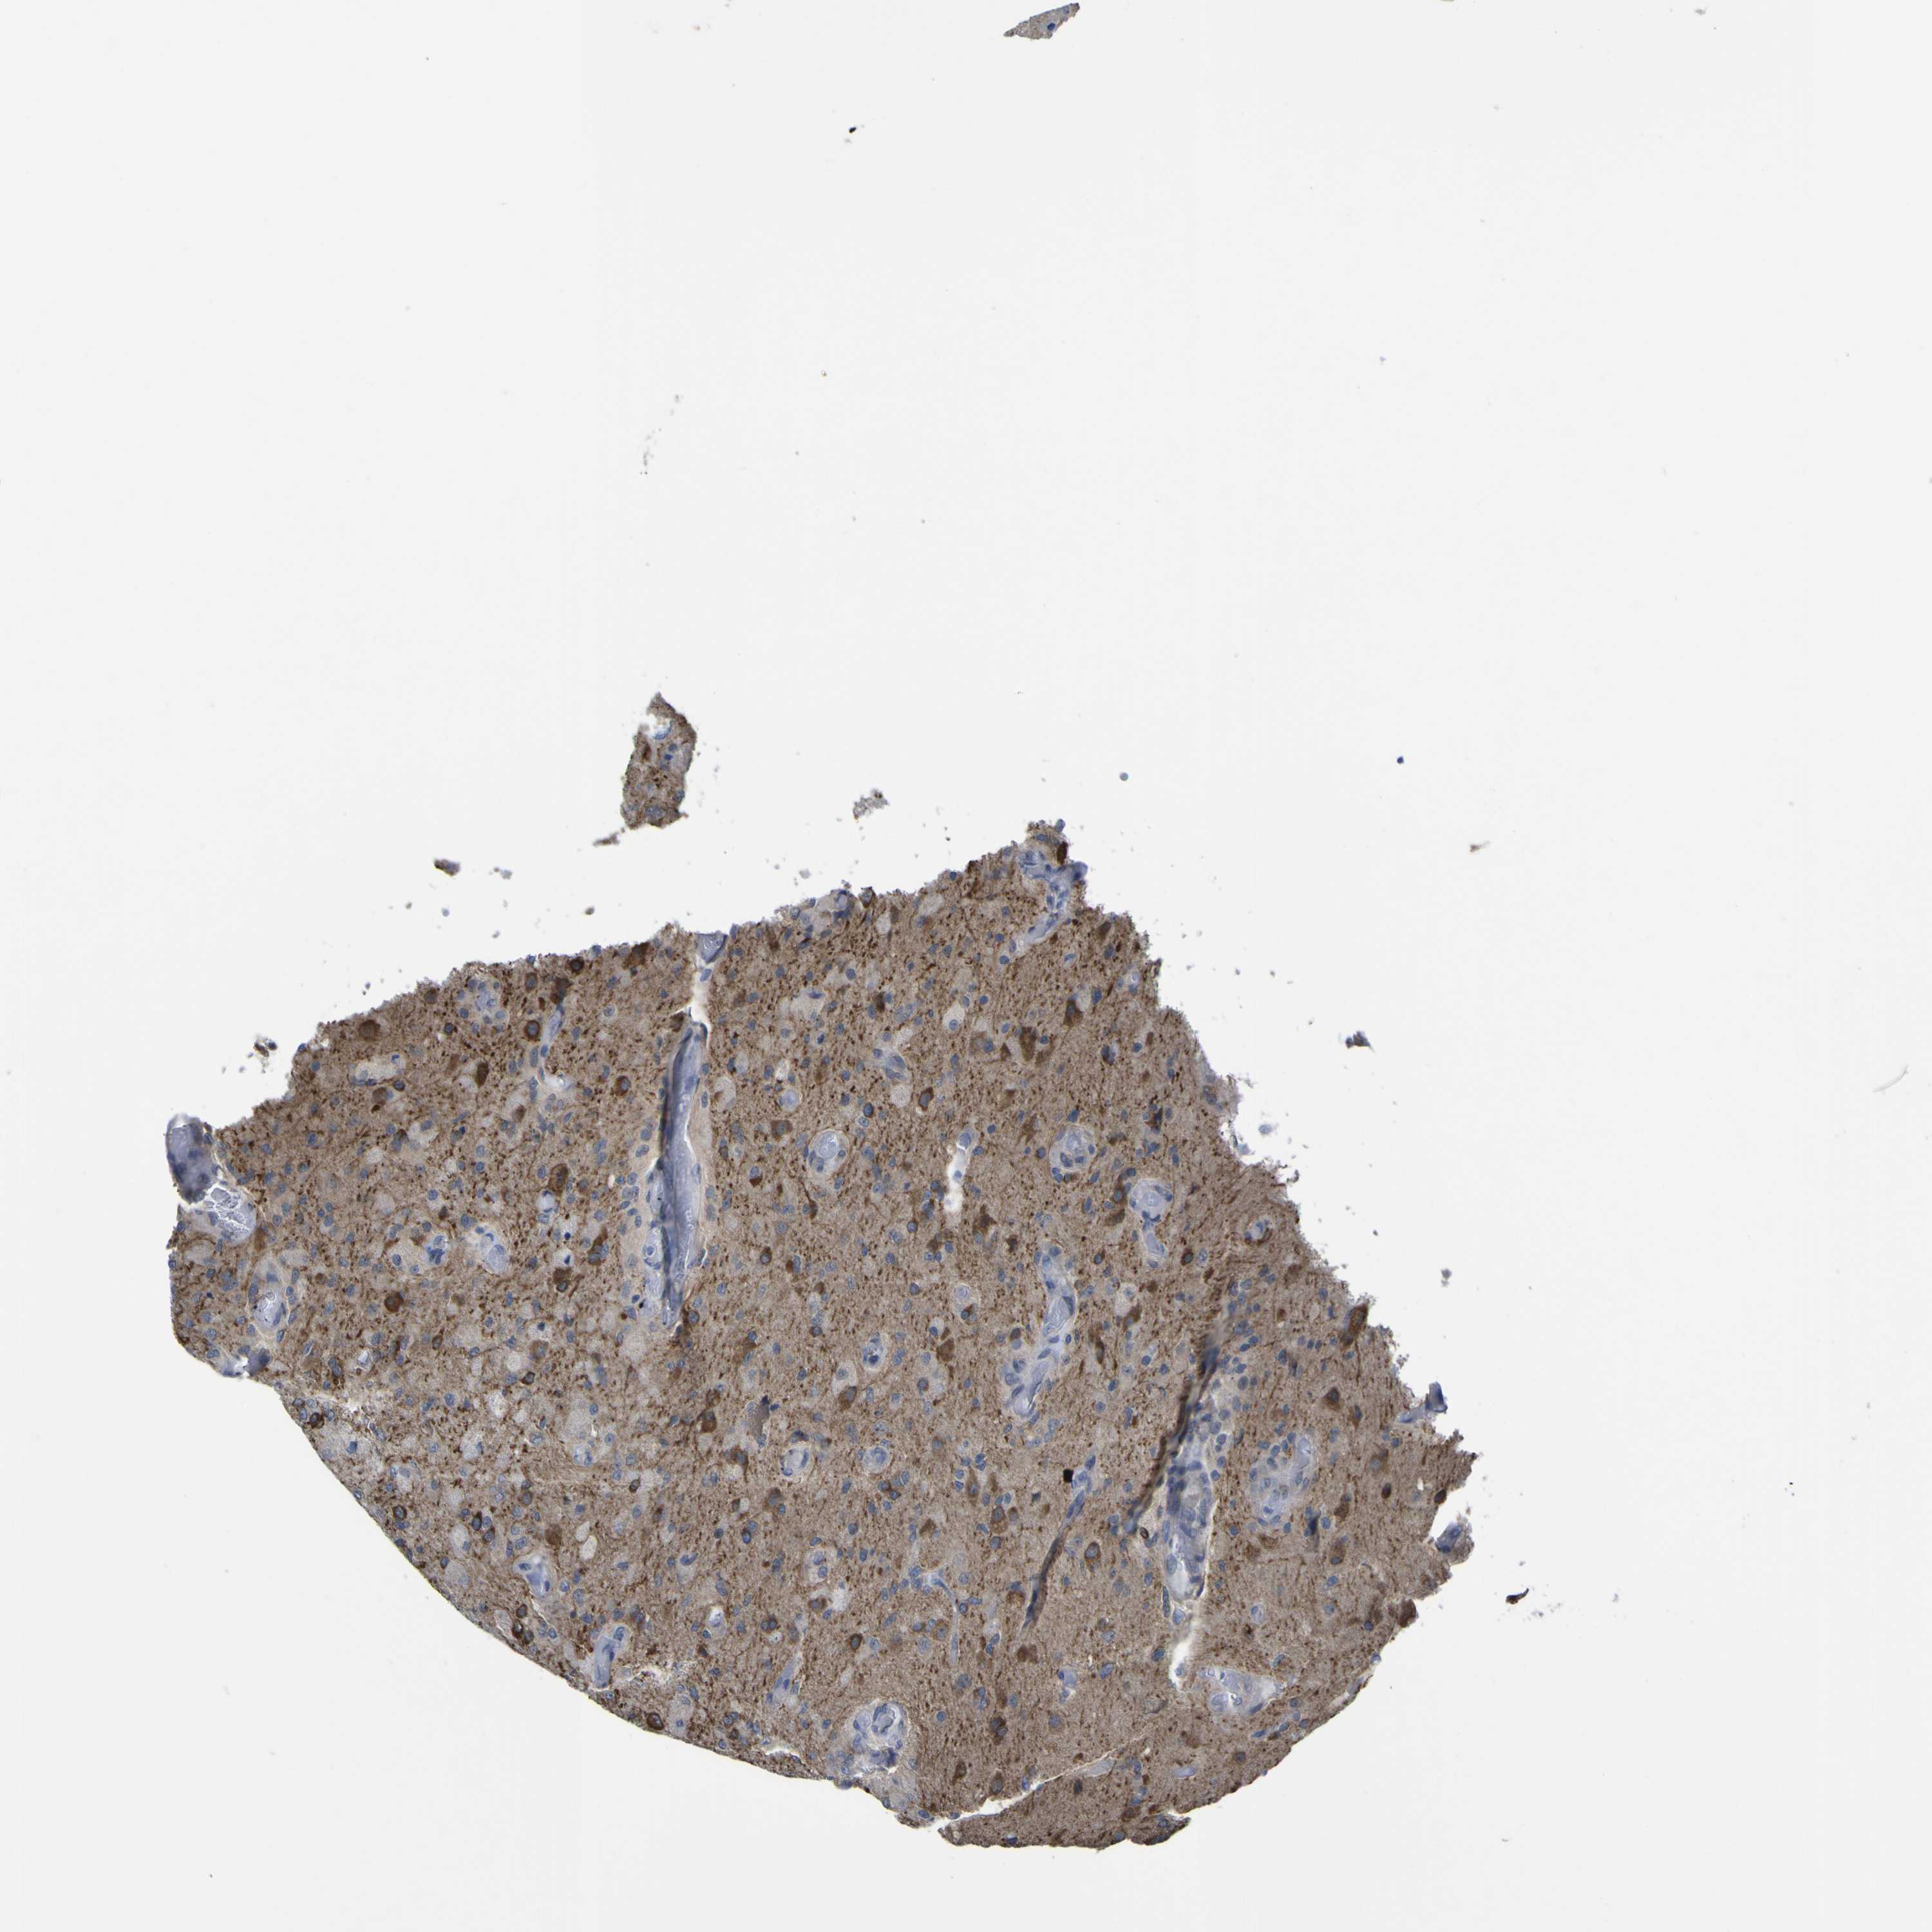

GLIOMA - Protein expressioni

A mouse-over function shows sample information and annotation data. Click on an image to view it in a full screen mode. Samples can be filtered based on level of antibody staining by selecting one or several of the following categories: high, medium, low and not detected. The assay and annotation is described here.

Note that samples used for immunohistochemistry by the Human Protein Atlas do not correspond to samples in the TCGA dataset.

Antibody stainingi

Antibody staining in the annotated cell types in the current human tissue is reported as not detected, low, medium, or high, based on conventional immunohistochemistry profiling in selected tissues. This score is based on the combination of the staining intensity and fraction of stained cells.

Each image is clickable and will lead to virtual microscopy that enables deeper exploration of all samples and also displays staining intensity scores, fraction scores and subcellular localization as well as patient and tissue information for each sample.

Antibody CAB010391

Staining

High

Medium

Low

Not detected

Intensity

Strong

Moderate

Weak

Negative

Quantity

>75%

75%-25%

<25%

None

Location

Nuclear

Cytoplasmic/membranous

Cytoplasmic/membranous,nuclear

Glioma, malignant, High grade

Glioma, malignant, Low grade